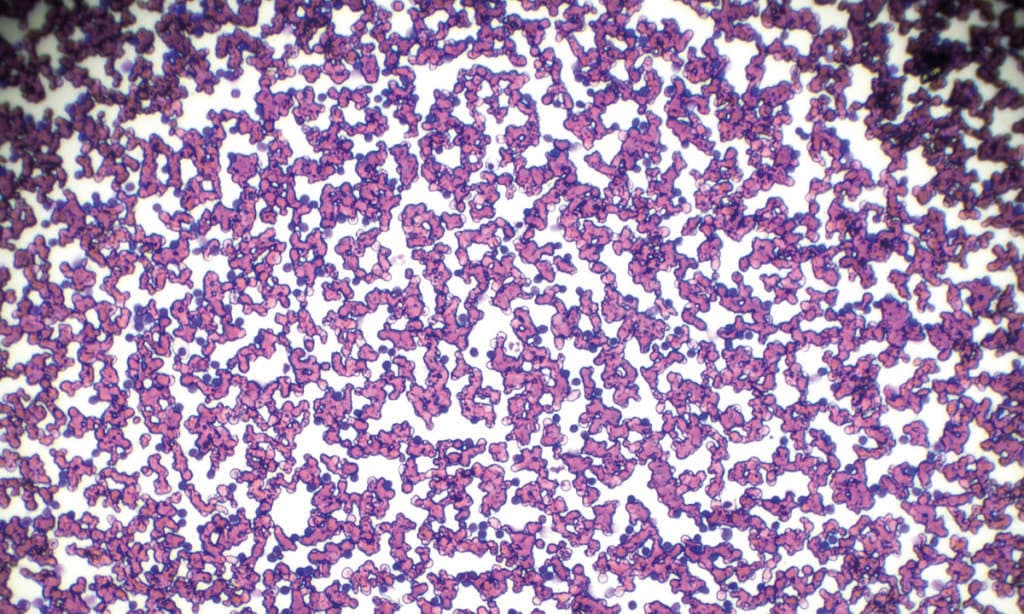

Chronische lymphatische Leukämie (CLL) Blutausstrich unter Lichtmikroskopie